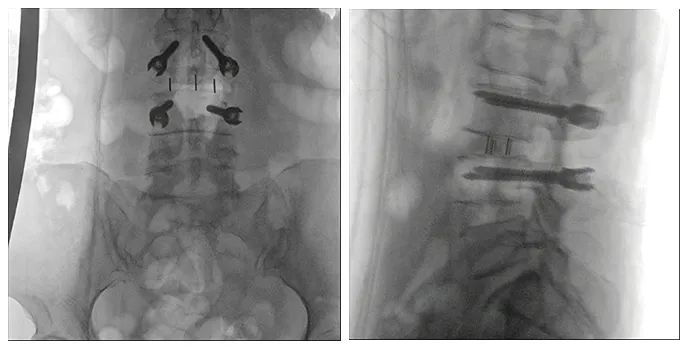

使用普爱医疗术中三维导航C臂进行透视,根据透视影像引导确认责任间盘、规划手术方案,充分暴露骨组织,并通过专业器械切除椎板,暴露神经及椎管;在C形臂的引导下,确定责任间盘上下椎体椎弓根位置,制定进针点及进针方向,沿椎弓根方向植入脊柱螺钉进行固定;放入椎间融合器,加固螺钉。最后再进行C形臂透视,确认手术的完成效果。

手术效果确认